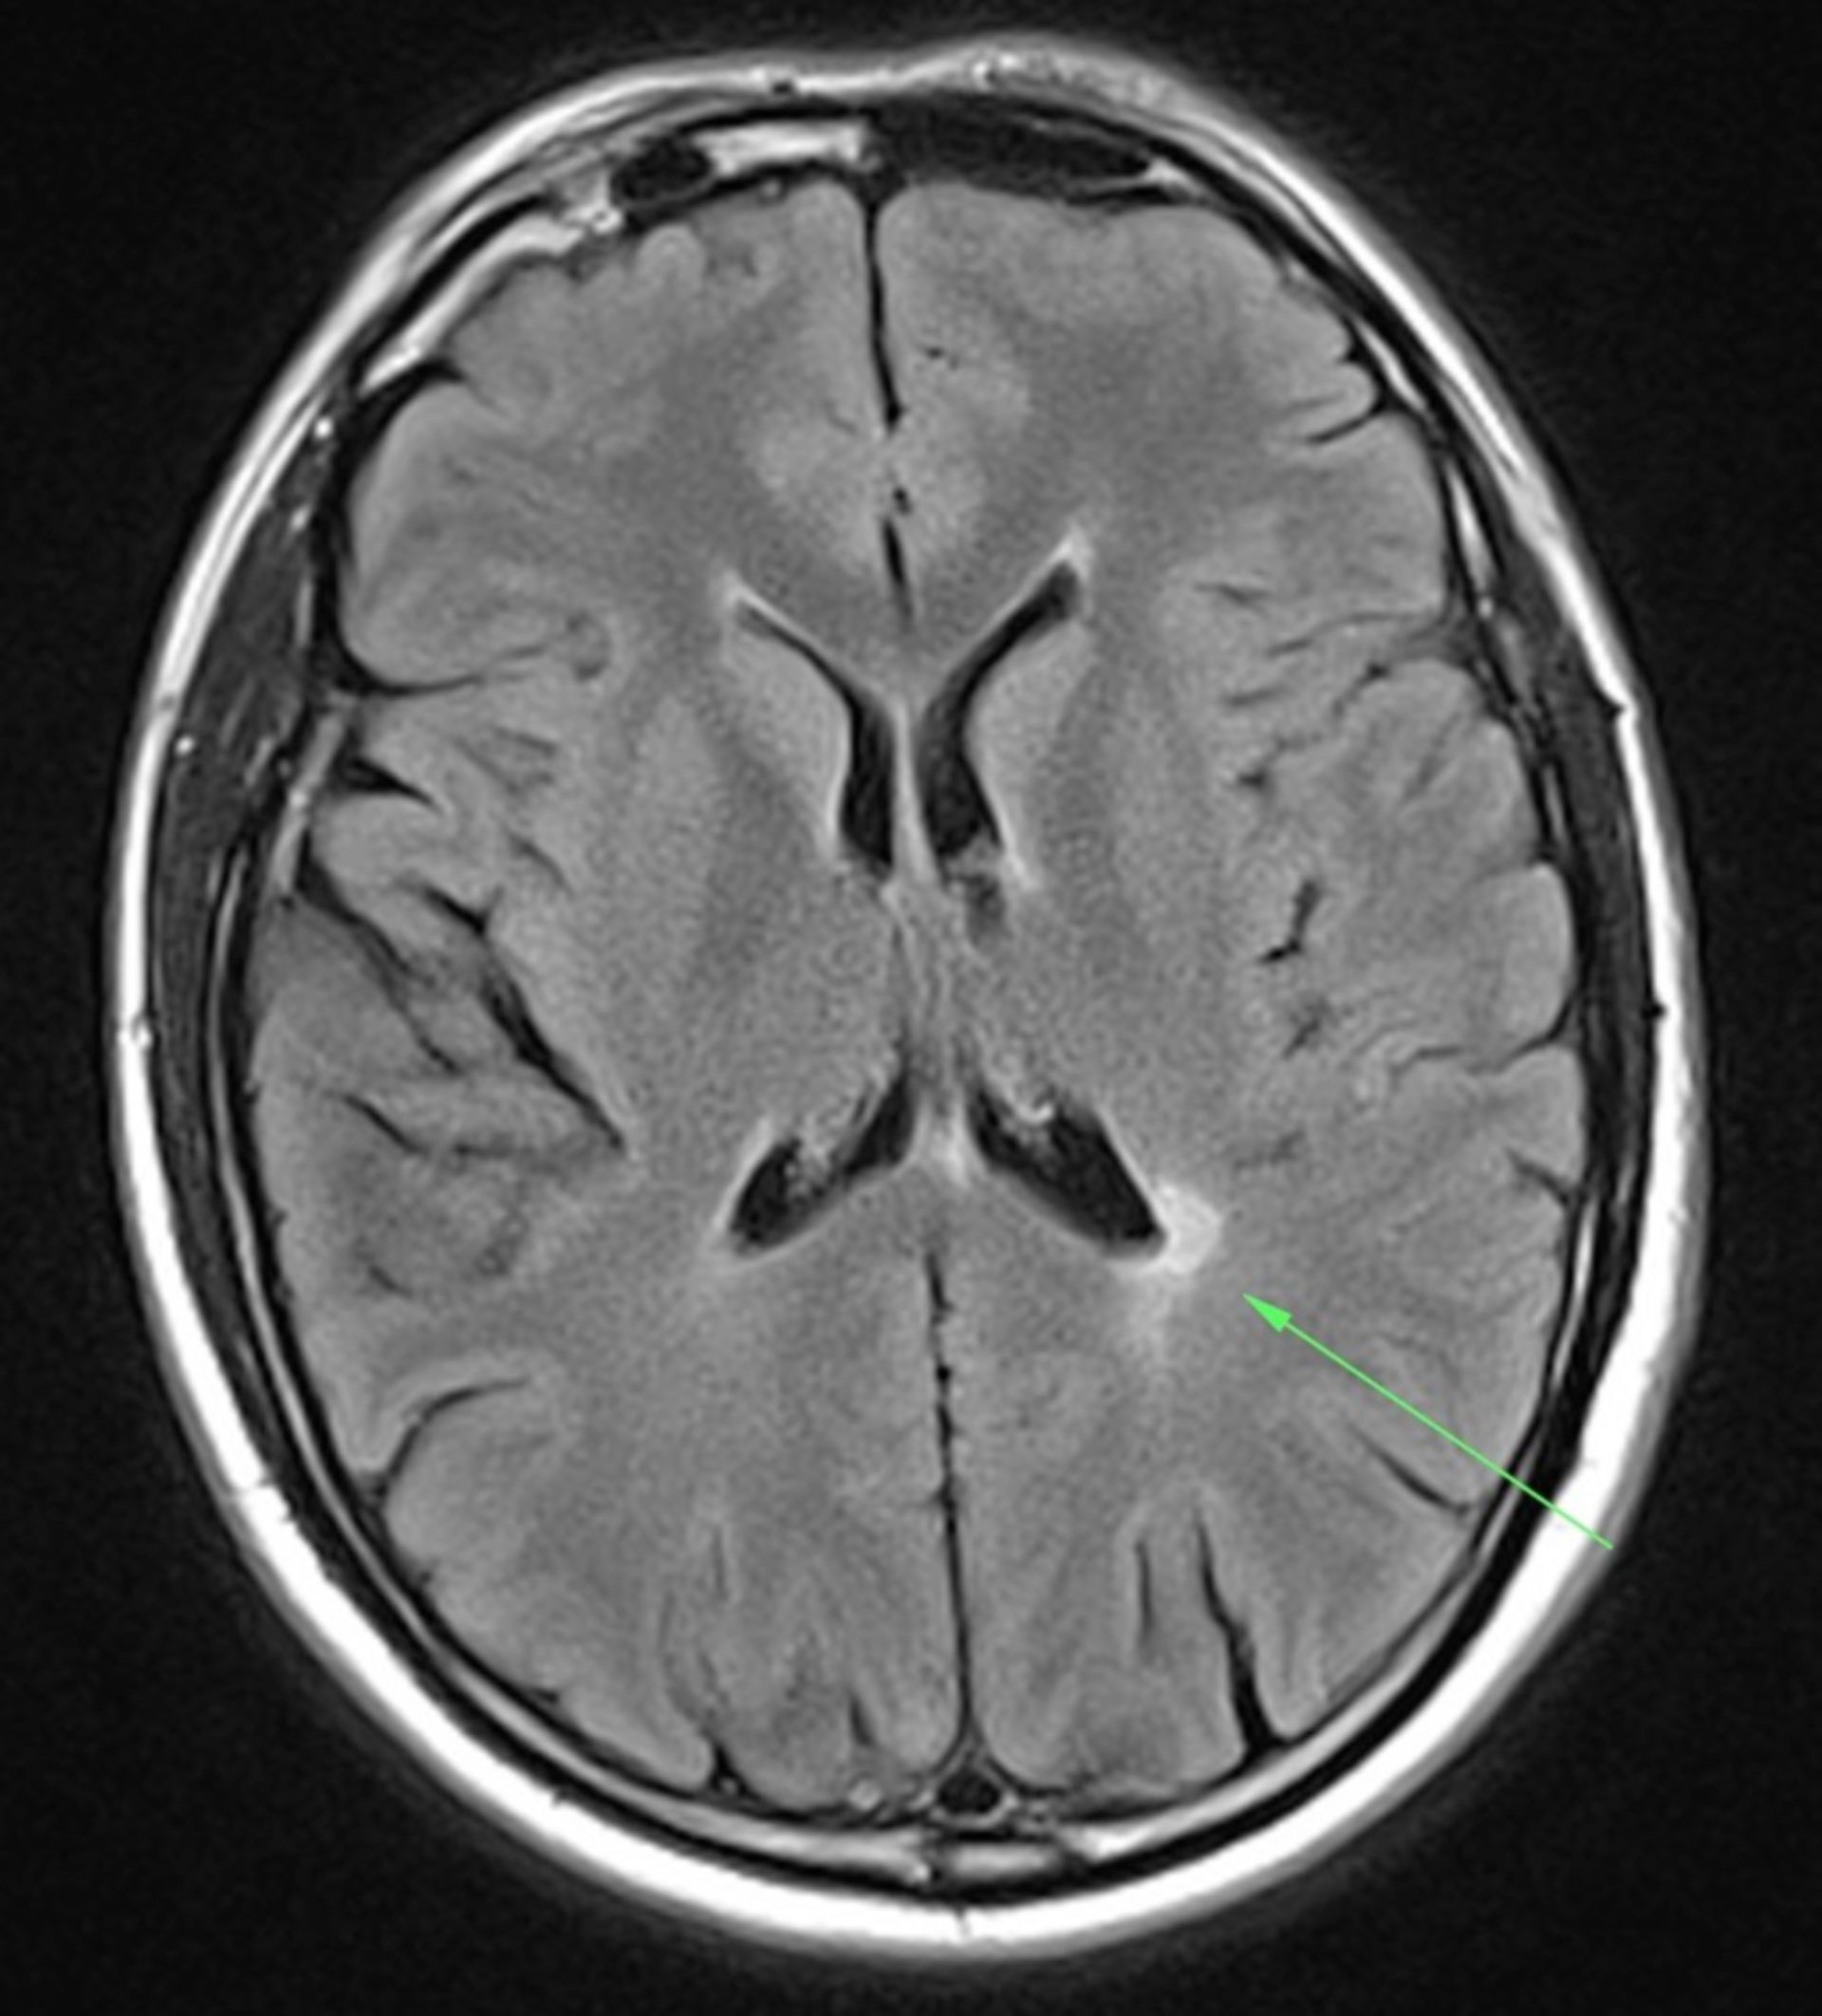

Beim MRT lagert sich giftiges Metall im Gehirn ab – WELT Mrt 7 route map – Mrt 7 stations map (Republic of Singapore)

MRT Schädel – DocCheck MRT Bild, könnte das ein Tumor sein? Kennt sich jemand damit aus? Könnte die helle Fläche ein …

MRT Schädel – DocCheck Sichere Prostatavorsorge mittels MRT-Untersuchung der Prostata

MS Herd MRT (1) – DocCheck Medizin – Gesundheit: Nierenzysten in MRI Abdomen medizinisches Bild

MRT Schädel – DocCheck #MRT: Sungai Buloh – Kajang Line Phase 1 To Officially Start 16th December – Hype Malaysia

MRT 4 Schädel – DocCheck Taipei MRT Roadmap